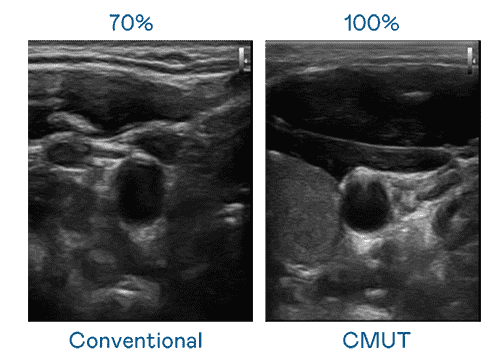

CMUT 技术是一种用电容式微机电元件来产生超音波讯号的技术。。。。与传统 PZT 压电式技术相比,,CMUT 频宽增加 30%,,,更宽频的超音波讯号让影像解析度大幅提升,,是实现高影像品质医疗超音波扫描、、促进精准医疗发展的关键技术。。。。

大频宽带来超清晰影像

超音波影像的解析度高低,,,,首先取决于探头能发出的讯号频宽。。。尊时凯龙 CMUT 可提供高清晰的超音波讯号,,,提供高频宽、、、高灵敏度、、、影像纹理细节更高的超音波影像,,协助医护人员缩短影像判读时间及利用精准的医疗影像进行诊断。。。